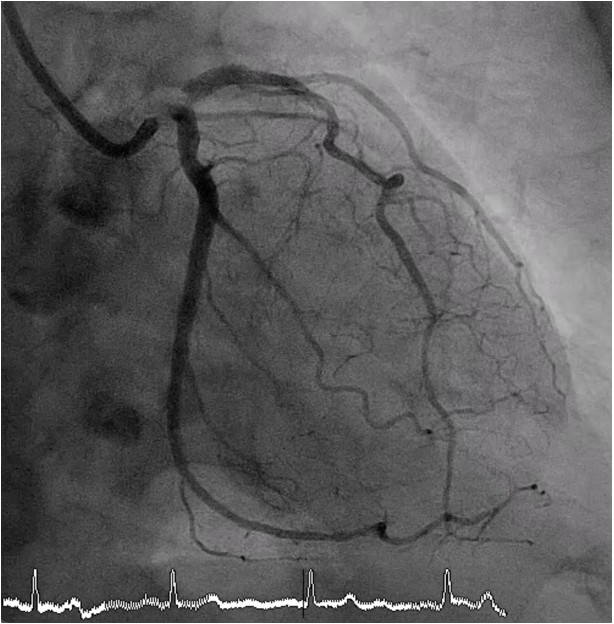

Coronary angiography revealed critical stenosis of the distal left main with calcified nodule at the left main bifurcation (Medina 1-1-1), 90% stenosis at ostial LAD and 90% stenosis at ostial LCx.

A 7 Fr JL 4.0 guiding catheter was engaged into LCA via RFA. We planned to perform PCI at LM bifurcation with Culotte technique. We successful wired to distal LAD using Finecross microcatheter with Conquest Pro guidewire (Failed using Sion blue, Fielder XT and Gaia Next2 guidewires). The microcatheter could not pass LAD lesion. Successfully passed the lesion using Tornus microcatheter. Then we exchanged RotaWire Floppy wire. Rotational atherectomy was done at LM-proximal LAD with Burr 1.25 mm at 180,000 rpm total 2 runs and step up Burr to 1.75 mm at 180,000 rpm total 2 runs for further debulking. Then we wired to LAD with Sion blue and LCx with Sion guidewires. IVUS was performed in LM, LAD and LCx. IVUS from LM-LAD showed eruptive calcified nodules with cracked calcific plaques and reverberation with MLA 2.86 mm2. IVUS from LM-LCx showed MLA 4.6 mm2. We prepare the lesion LM-LAD with non-compliant 4.0/15 mm balloon at 20 atm. A 4.0/18 mm stent was deployed from LM to LAD then re-wiring. We prepare the LM-LCx with semi-compliant 2.0/15 mm balloon (for opening strut) at 14 atm, 2.5/15 mm balloon at 14 atm and non-compliant 4.0/15 mm balloon at 20 atm. A 4.0/23 mm stent was deployed from LM to LCx. The KBI was performed with non-compliant 4.0/15 mm balloons at 10 atm. POT was performed with non-compliant 4.0/15 mm balloon at 14 atm. Final angiogram showed good coronary blood flow and IVUS demonstrated well stent expansion, no malapposition and no stent edge dissection.